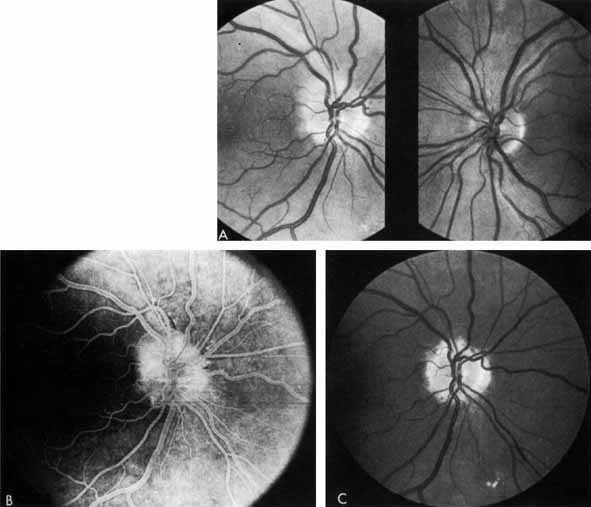

Fig. 3 A. Diabetic retinopathy with multiple microaneurysms, dot hemorrhages, and early neovascularization of the optic disc (NVD). A small blot hemorrhage is seen inferiorly. B. Continued. Midphase of the fluorescein angiogram. Patent microaneurysms are seen as hyperfluorescent dots. Note that most microaneurysms cannot be seen ophthalmoscopically. There is some enlargement of the foveal avascular zone because of some occluded capillaries. Temporally there is a larger zone of capillary nonperfusion. The NVD is beginning to leak. C. Late phase of the fluorescein angiogram showing diffuse leakage of fluorescein into the macula.

It is often difficult to distinguish a small dot hemorrhage from a microaneurysm by ophthalmoscopy alone. On fluorescein angiography patent microaneurysms will fill with dye quickly and then leak,5 unlike a small dot hemorrhage that will block fluorescence (see Fig. 3). However, angiography cannot distinguish a hemorrhage from a microaneurysm filled with clotted blood. Because fluorescein passes easily though them, we usually see many more microaneurysms on fluorescein angiography than are apparent on examination.6

When the wall of a capillary or microaneurysm is thin, it may rupture, giving rise to an intraretinal hemorrhage. If the hemorrhage is deep (i.e., in the inner nuclear layer or outer plexiform layer), it usually has a round or oval shape (“dot or blot”) (see Fig. 3). Superficial (nerve fiber layer) hemorrhages, on the other hand, become flame- or splinter-shaped indistinguishable from that seen in hypertensive retinopathy. Although people with diabetes with normal blood pressure may have multiple splinter hemorrhages, they should nevertheless have their blood pressure checked because a frequent complication of diabetes is systemic hypertension.